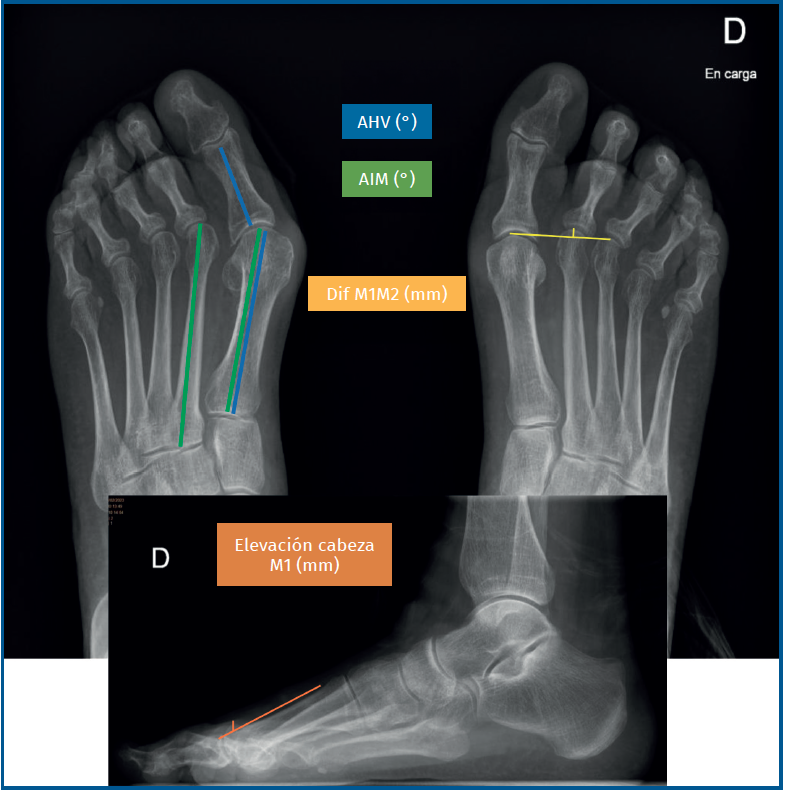

Descripción de las medidas radiológicas (Figura 1)

- AHV: definido como el ángulo entre el eje del M1 y la F1.

- AIM: definido como el ángulo entre los ejes de los metatarsianos; se mide en este estudio el ángulo entre el primer y el segundo metatarsianos (M1-M2).

- Acortamiento relativo de M1: se mide según el método descrito por Coughlin. Consiste en el trazo de una línea que va del centro de la cabeza de M1 a la cabeza de M3; se mide la distancia desde el centro de la cabeza de M2 hasta esta línea de referencia(7).

- Elevación de la cabeza de M1: se mide en la radiografía de perfil en carga. Consiste en el trazo de una línea siguiendo la cortical dorsal del M1 y otra línea perpendicular al plano del suelo y que pasa por el punto más alto de la cabeza metatarsiana. Se mide la distancia desde el punto más alto de la cabeza y el punto de cruce de las 2 líneas. La diferencia de esta distancia entre el pre- y el postoperatorio se considera la elevación de la cabeza(4).

- Posición de los sesamoideos: se clasifica la posición del sesamoideo tibial según la clasificación de Hardy y Clapham, del 1 al 7 en función de su relación con el eje longitudinal del M1 (Figura 2)(5).